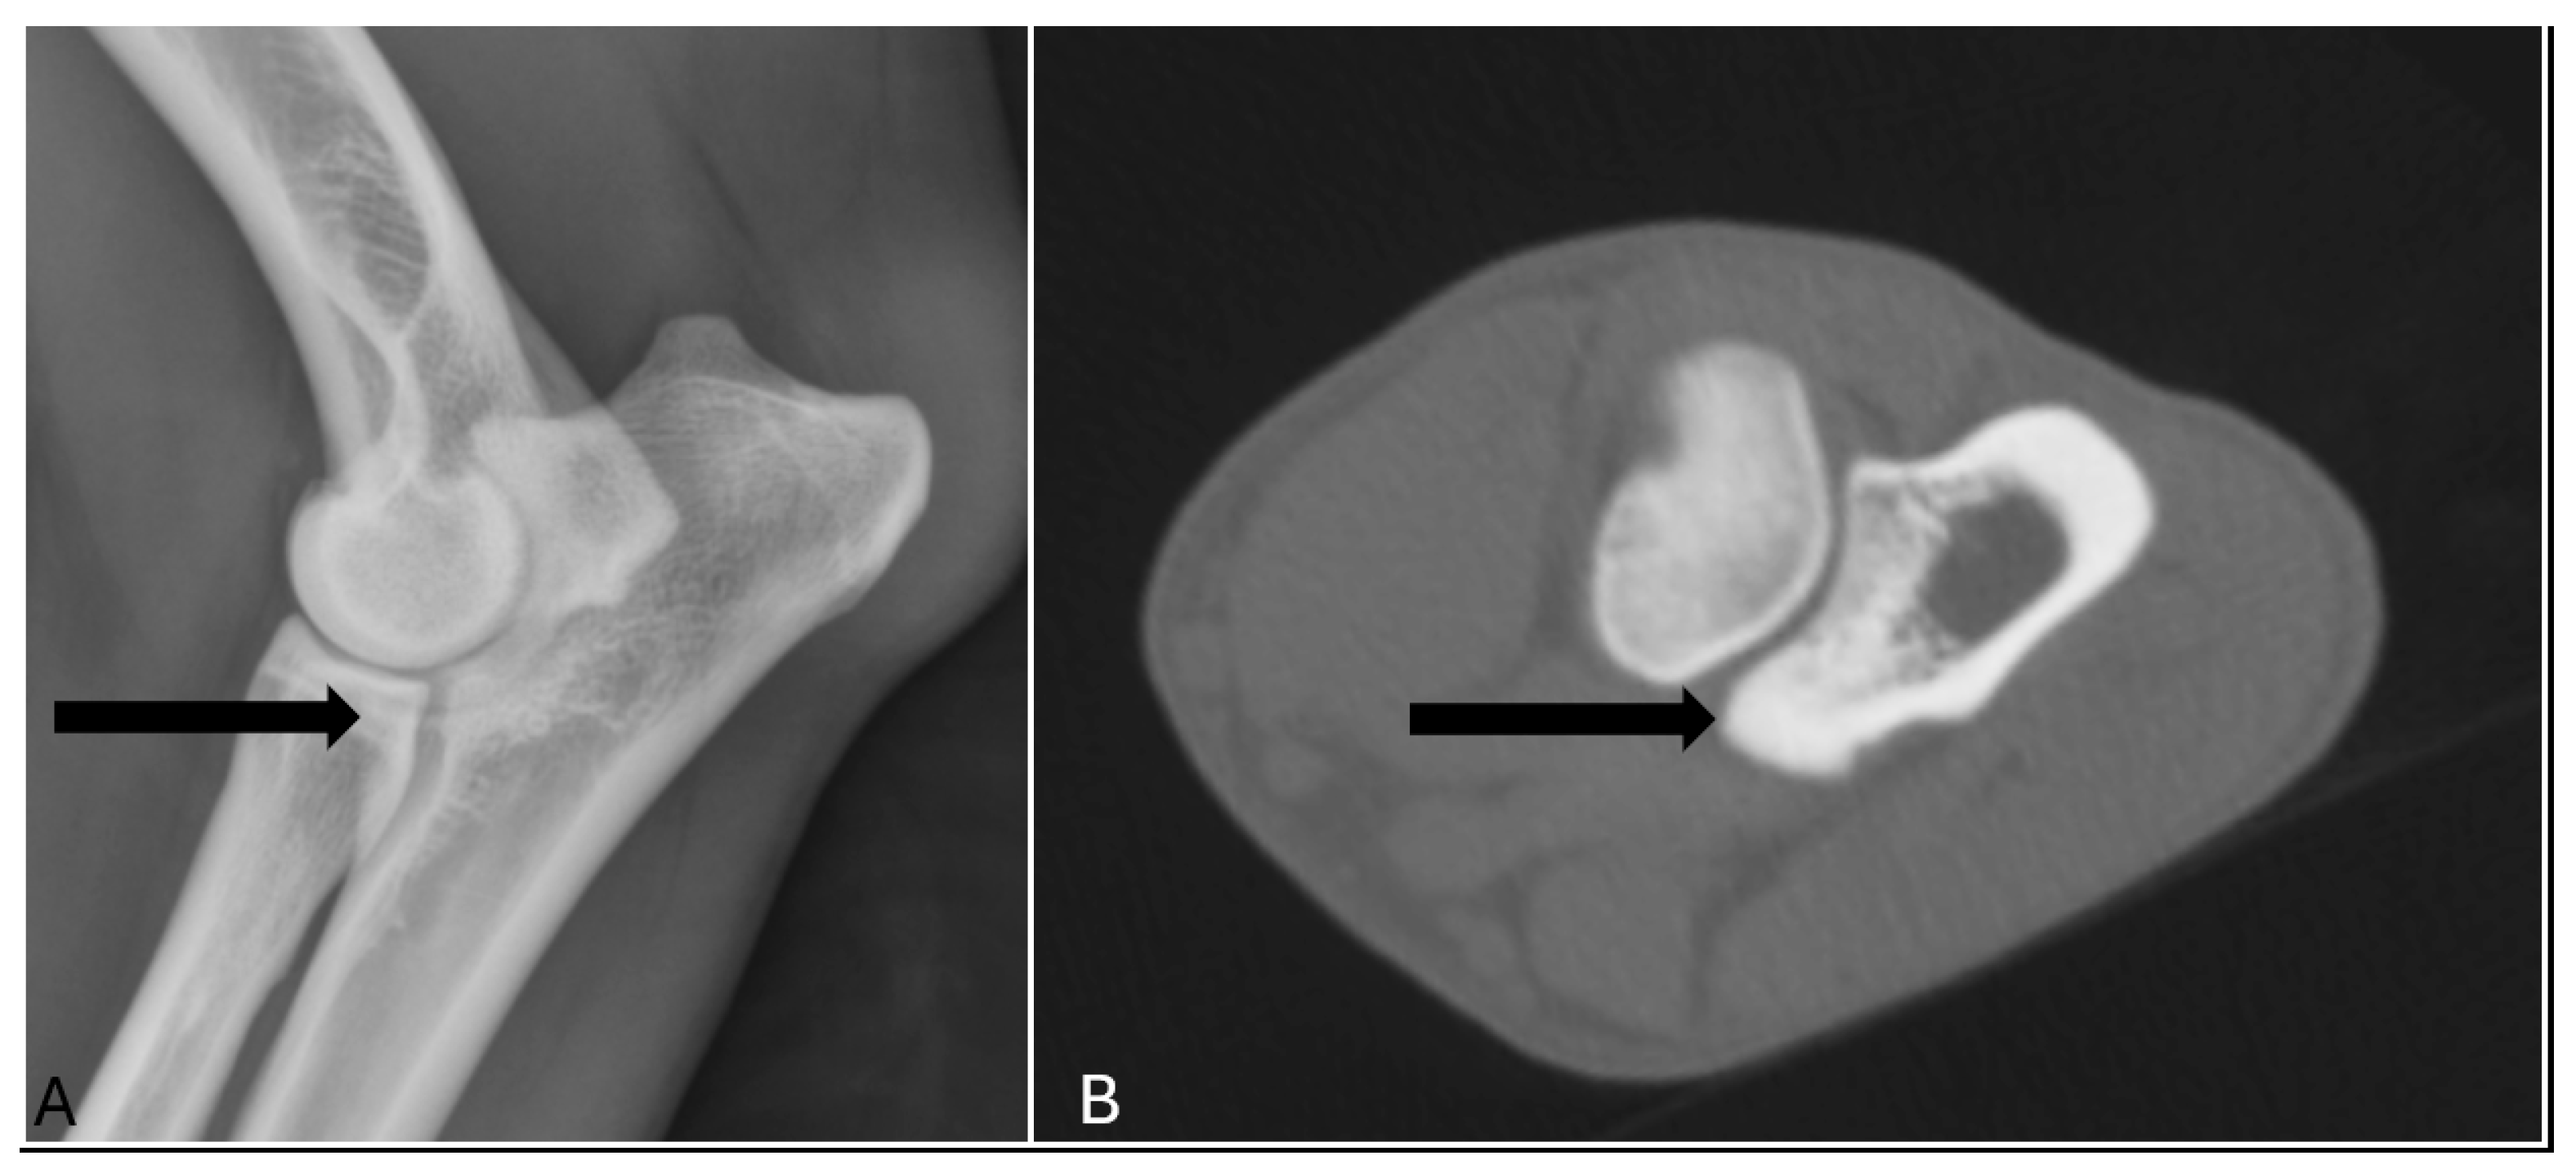

In terms of diagnostic accuracy, the comparison between radiographic and CT assessments revealed that radiography had a sensitivity of 65% (17/26) and a specificity of 93% (369/398) (Table 1). Specifically, nine elbow joints (9/26) were false negatives, meaning that MCD was detected in these joints only by CT and reported normal in radiography (Figure 1). Conversely, 29 joints (7%) were classified as false positives, indicating that radiography indicated the presence of MCD when in CT no abnormalities were detect. (Figure 2). The positive predictive value was 37% (17/46), while the negative predictive value was 98% (369/378) (Table 1).

Figure 2. The lateral radiograph and transverse image of the right elbow of a 17 months old labrador retriever which was classified as false positive, meaning that medial coronoid process (arrow) was scored abnormal only in radiography (A), and reported normal in CT (B).